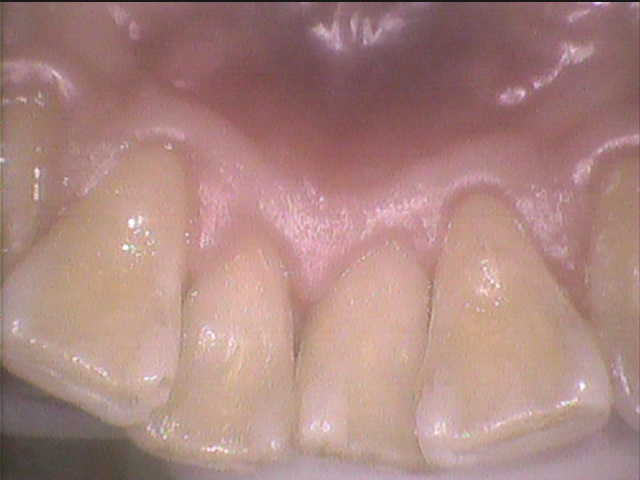

◎クリーニング後のお写真

綺麗になりました✨

久しぶりにクリーニングをした患者さんは歯石が多く、固くなってしまっていることがあるため

数回に分けて行うことが多いです。

個人差がありますが、だいたい3ヶ月~4ヶ月でまた新しい歯石がたまってきます。

定期的にクリーニングをしていきましょう!🦷